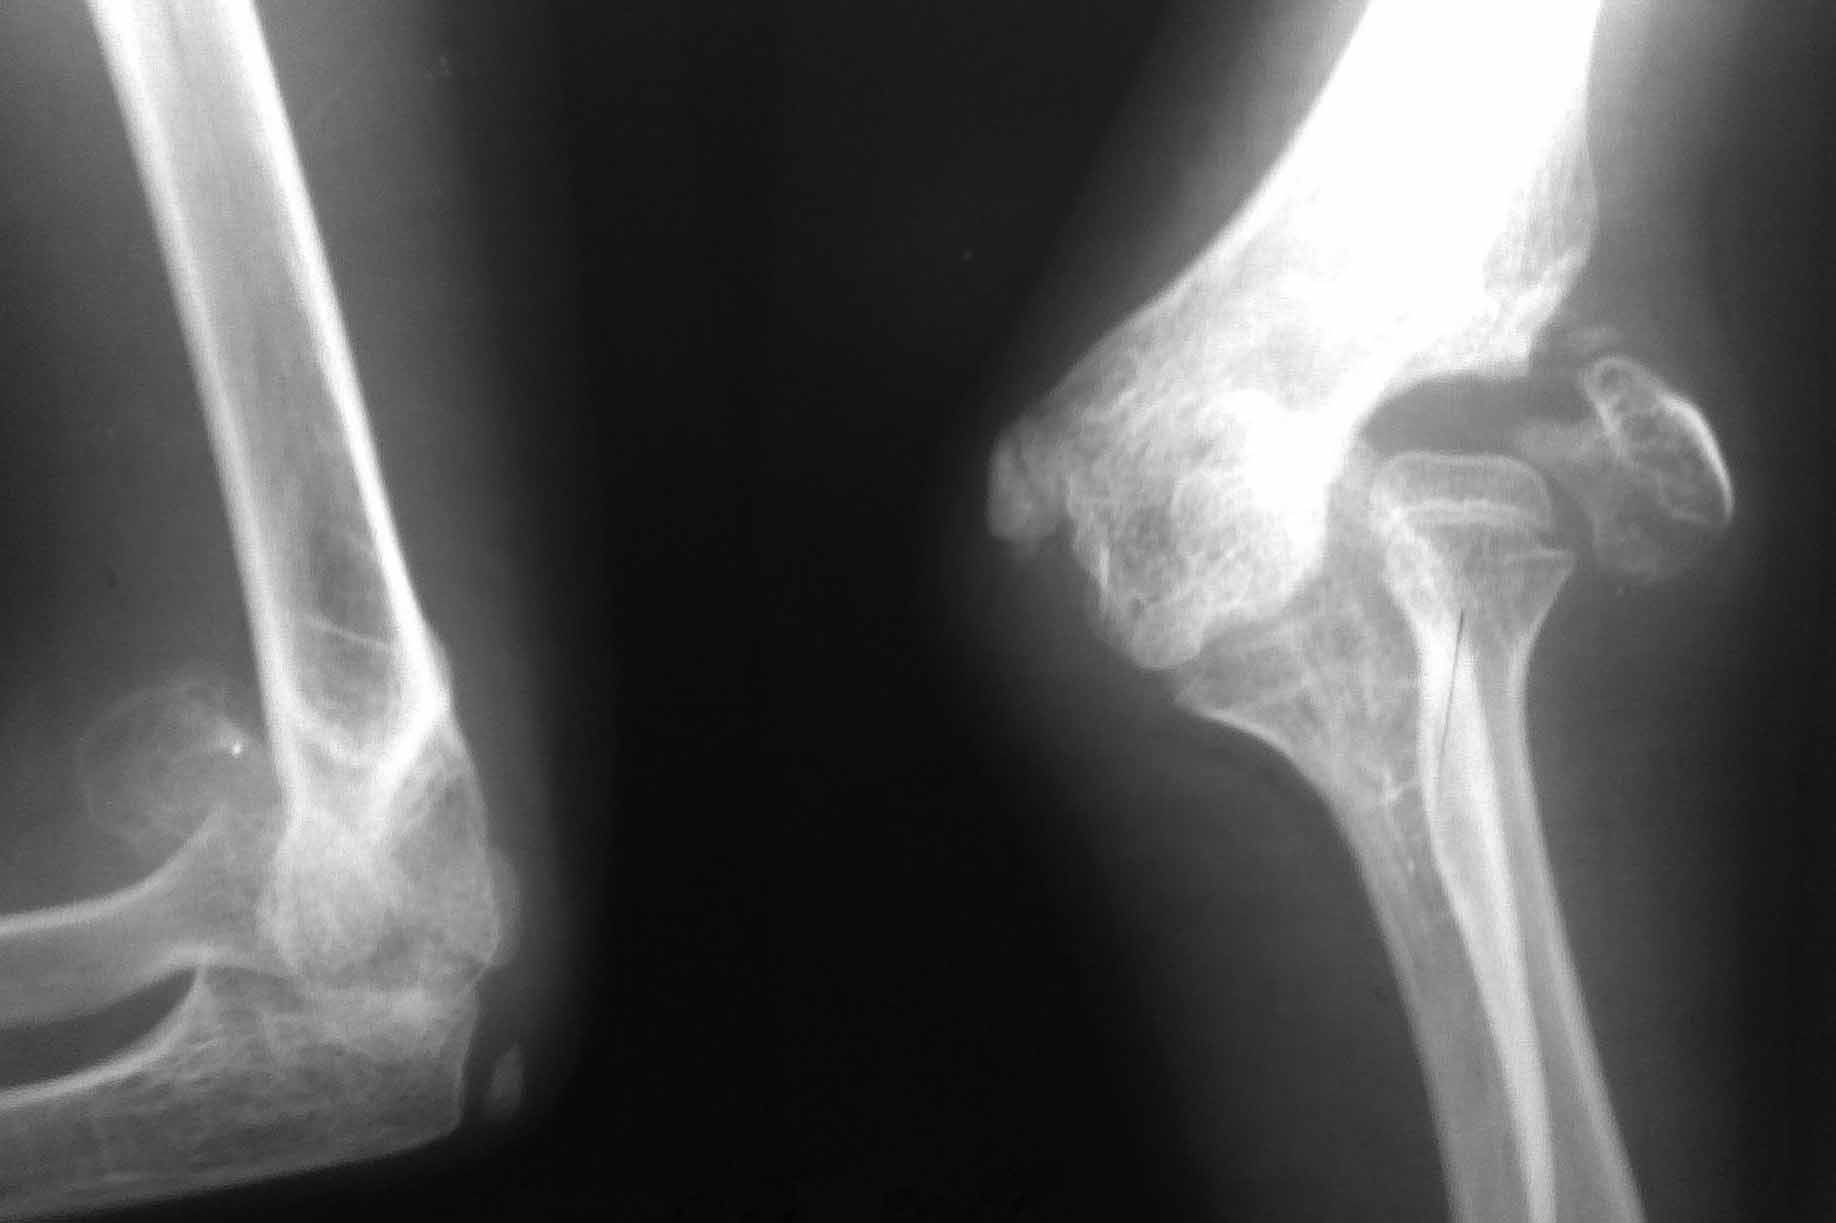

Уважаемые коллеги. Очень интересно услышать мнения по тактике лечения пациента 11 лет. DS:Ложный сустав головчатого возвышения правого плеча. Вальгусная деформация локтевого сустава Пациент 11 лет. Из детского дома. За помощью обратился впервые. Анамнез заболевания собрать не представляется возможным. Вероятнее всего имел место нелеченный перелом головчатого возвышения плеча со смещением отломков. Давность травмы неизвестна.

/Объективно: Вальгусная деформация локтевого сустава 25-30град. По наружной поверхности пальпируется тугоподвижный костный фрагмент головчатого возвышения. Функция сустава сохранена в полном объеме, безболезненна.Рентгенограмма прилагается.

Уважаемый господин Пожарский. Это конечно головчатое возвышение, ротированное кнаружи на 180 градусов.

Учитывая ситуацию самым надежным конечно будет корригирующая остеотомия в области дистального метафиза плечевой кости. На вопрос "когда" можно ответить встречным вопросом-зона роста мыщелка плечевой кости сохранена? Нет, не сохранена-значит можно уже сейчас.